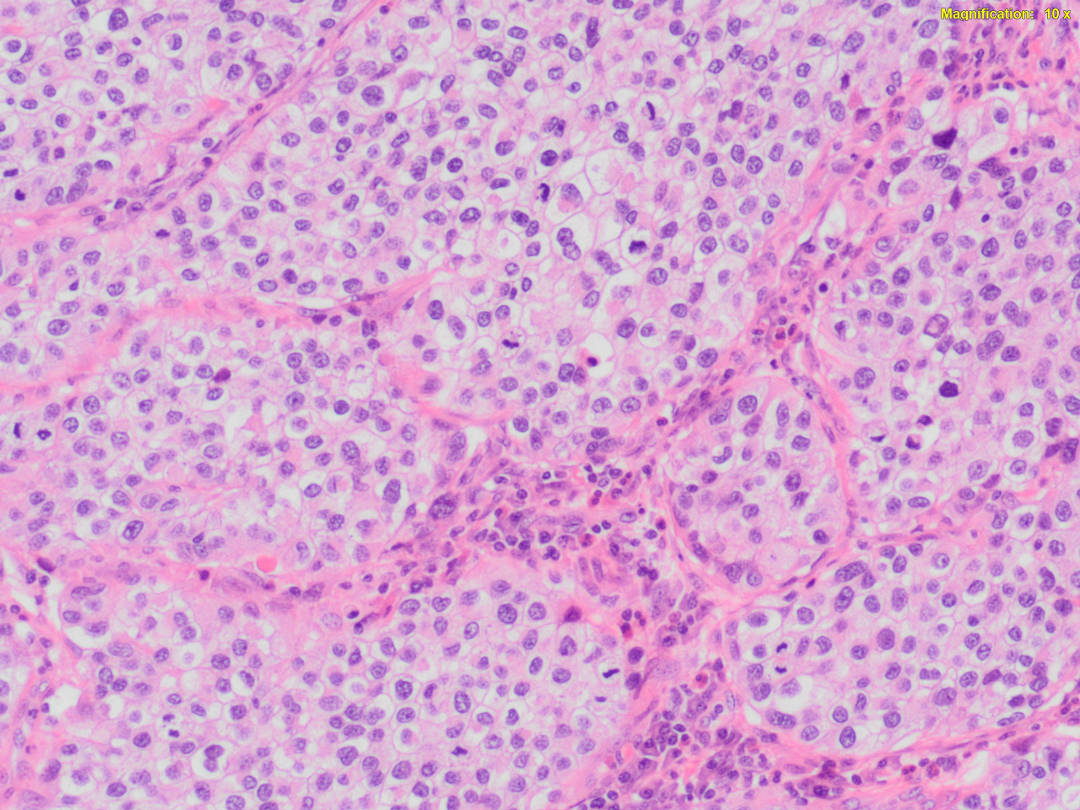

HematoPATOLOGíA.

La hematopatología realiza pruebas para ayudar a diagnosticar y tratar enfermedades neoplásicas y no neoplásicas de la sangre, la médula ósea y el sistema linfático.